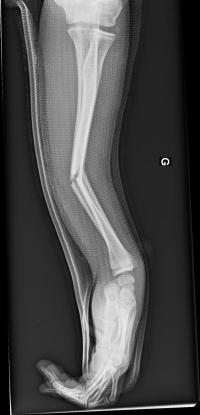

Fracture de l’avant-bras 31 mars 202519 mars 2024 par Damien Traitement Traitement orthopédique Embrochage centro-médullaire